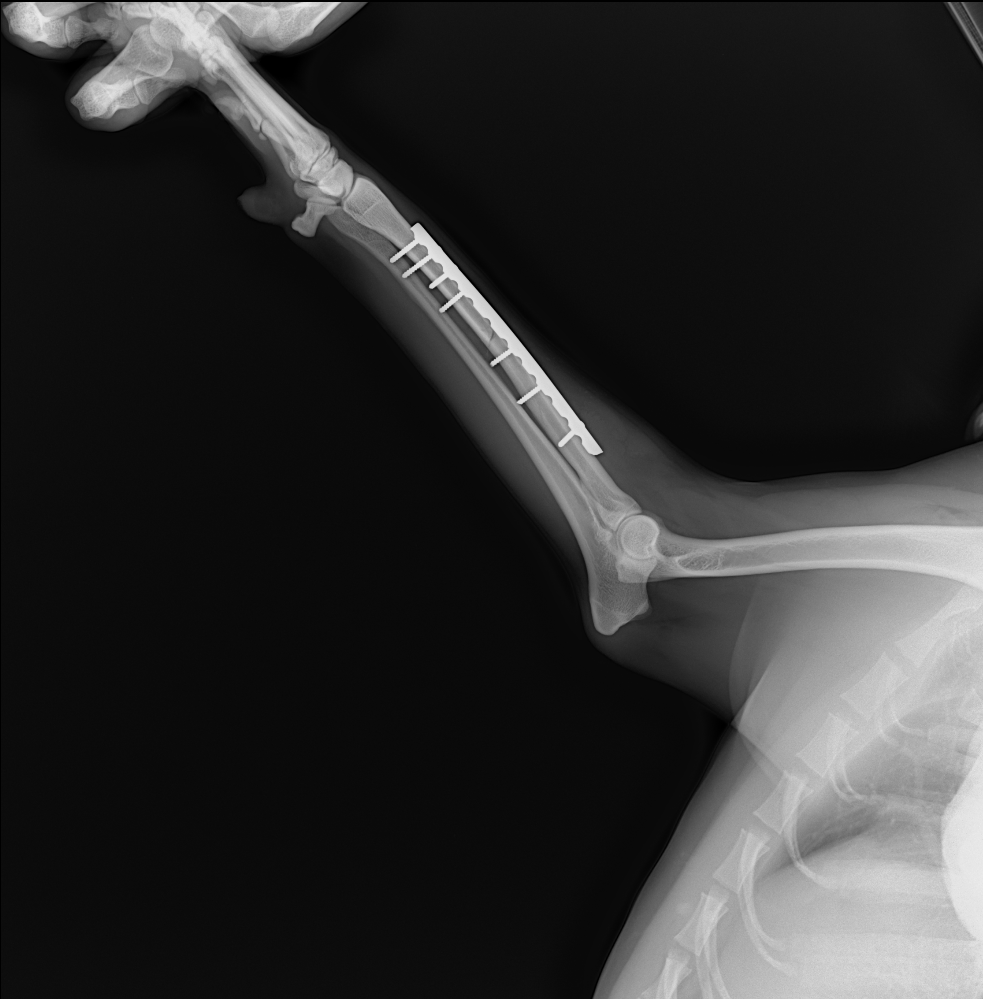

Share some clinical x-ray images by our veterinary DR system YSX056-PL with flat panel detector YSFPD-V1717X VET.

Here we'd like to share some clinical x-ray images by our veterinary DR system YSX056-PL with flat panel detector YSFPD-V1717X VET.